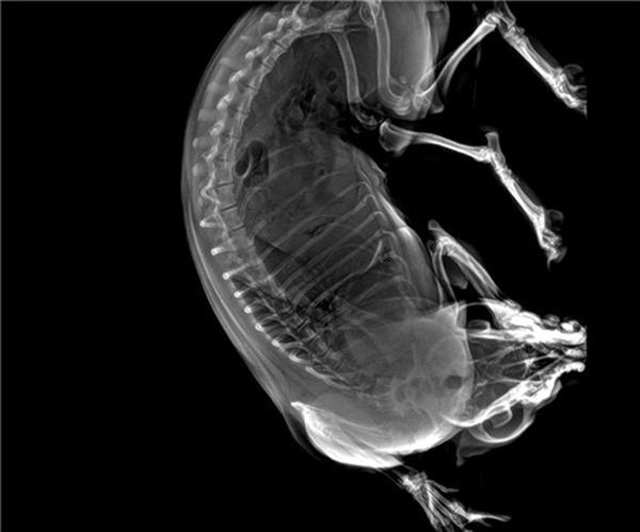

寵物DR的工作原理是X光線穿透動物體后在屏幕或者膠片上面顯示體內(nèi)影像。輔助寵物醫(yī)生讀片跟準確的治療,寵物DR顯示是寵物醫(yī)院診所的配置,提高了診斷的效率。DR的檢測效率比X線高44%,成像快采集時間10MS以下。3秒左右就可以看到檢查圖像。常規(guī)的胸部DR還要幾分鐘。所以寵物DR的出片速度是非常快的。很高的空間分辨率低噪音。可以獲得高清圖像,提高檢測正確率避免誤診等等問題。數(shù)字化圖像的優(yōu)勢是可以保留原始數(shù)據(jù),圖片識別,二三維的重建,醫(yī)學影像學實現(xiàn)全數(shù)字化和無膠片化鋪平了道路。提供照片打印服務(wù),防止照片丟失而重復(fù)照片。有針對性的對圖像進行處理,以提高診斷率。寵物DR的輻射量很低的,對人體的輻射風險不大。